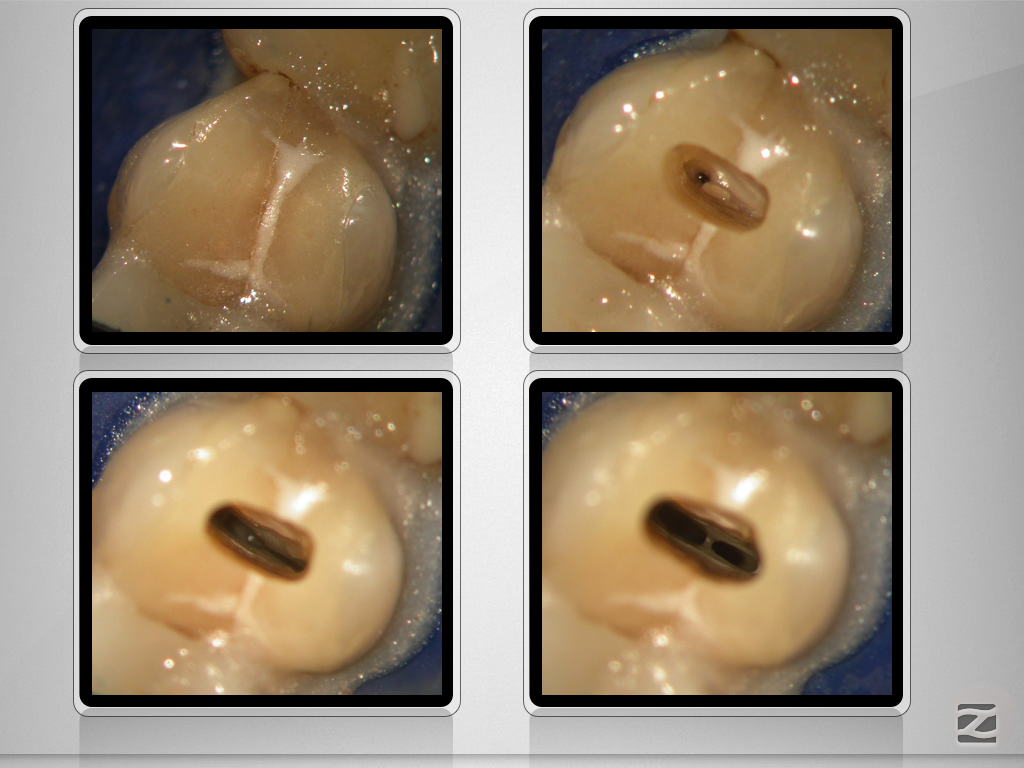

Vertucci Typ 3 / Typ 7